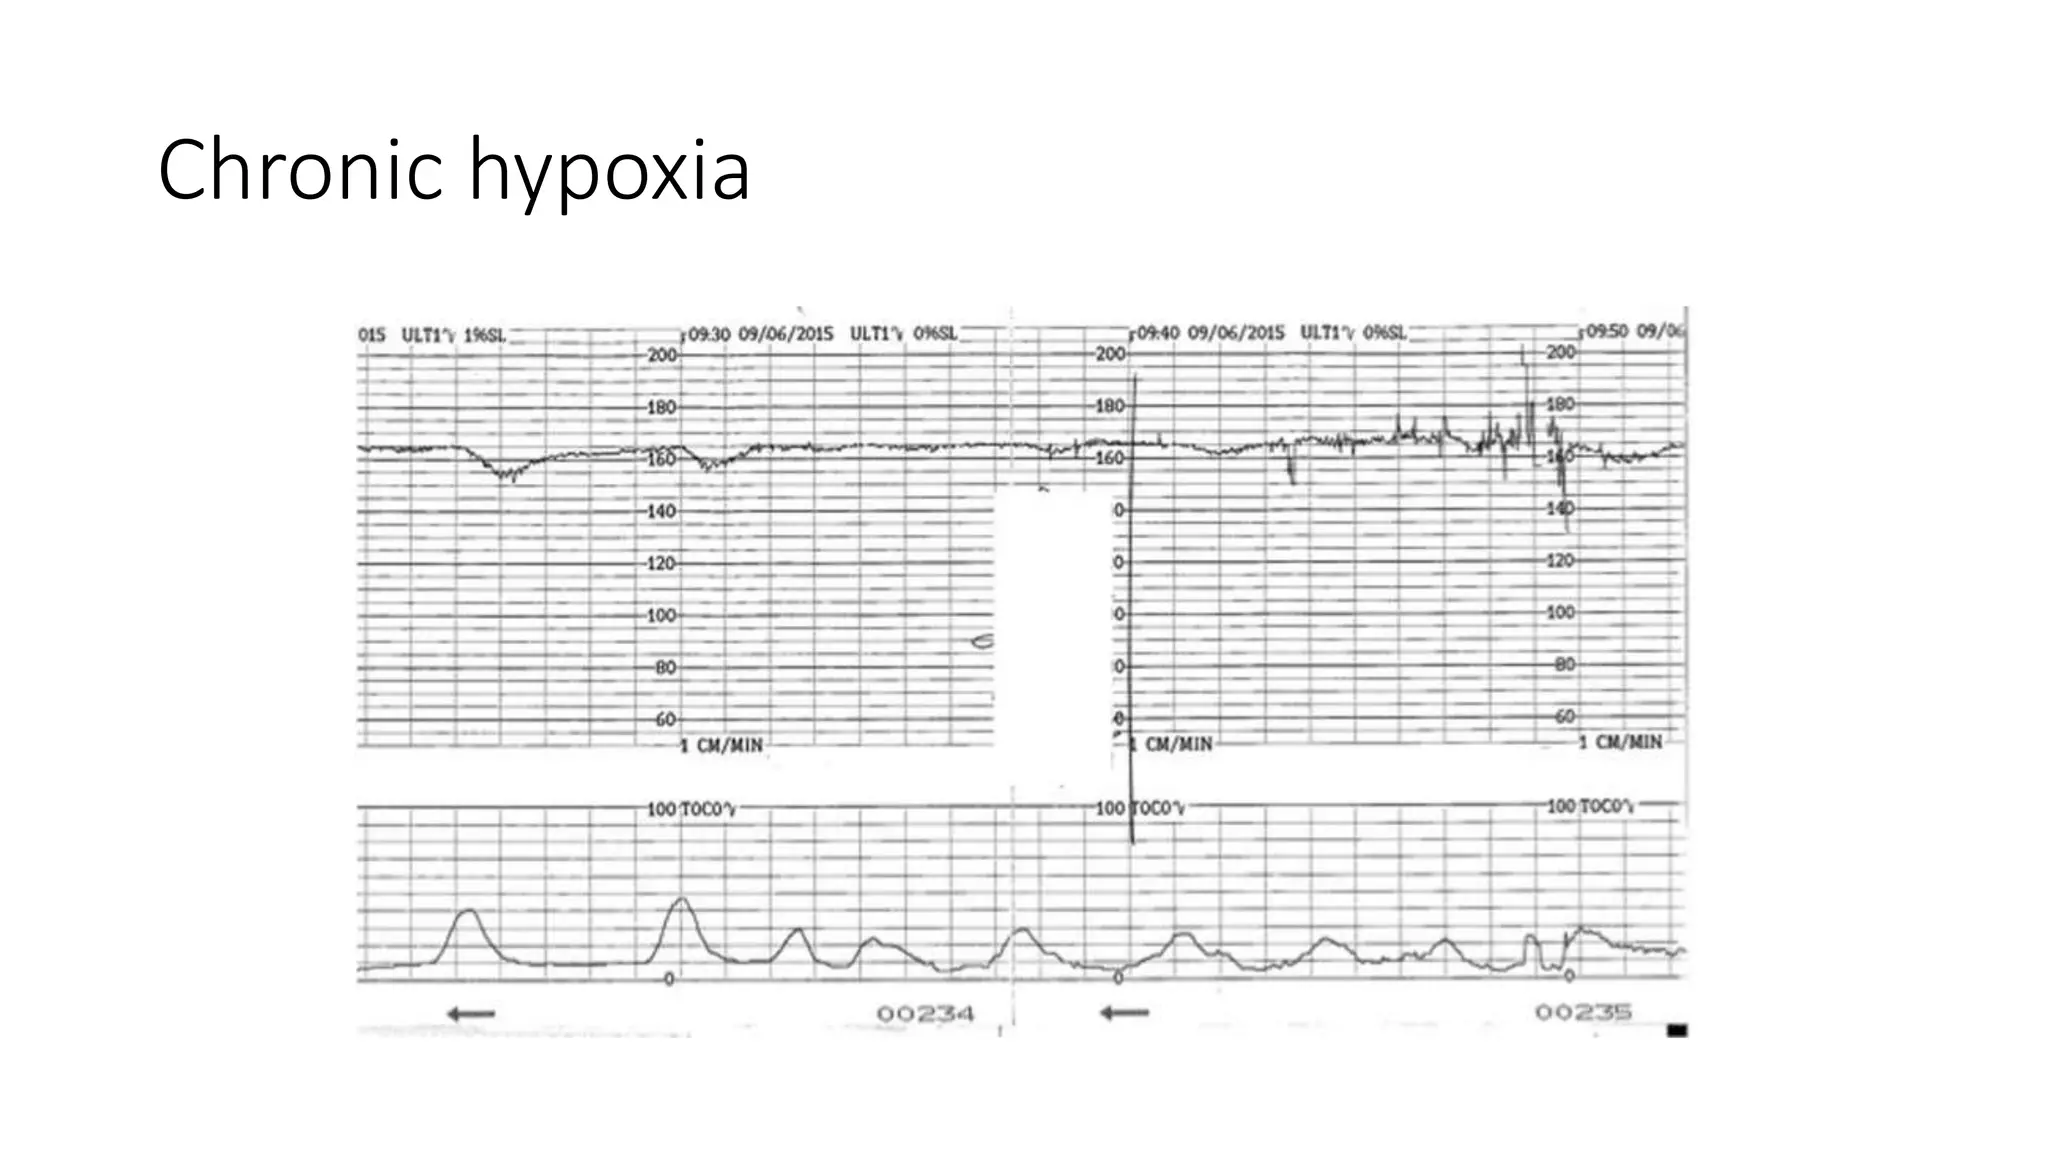

The document discusses key metrics for monitoring a baby's heart rate in utero, including the normal baseline rate of 100-160 bpm and variability. It also covers types of accelerations and decelerations that can occur, such as early or late, as well as bradycardia, which is an abnormally slow heart rate.